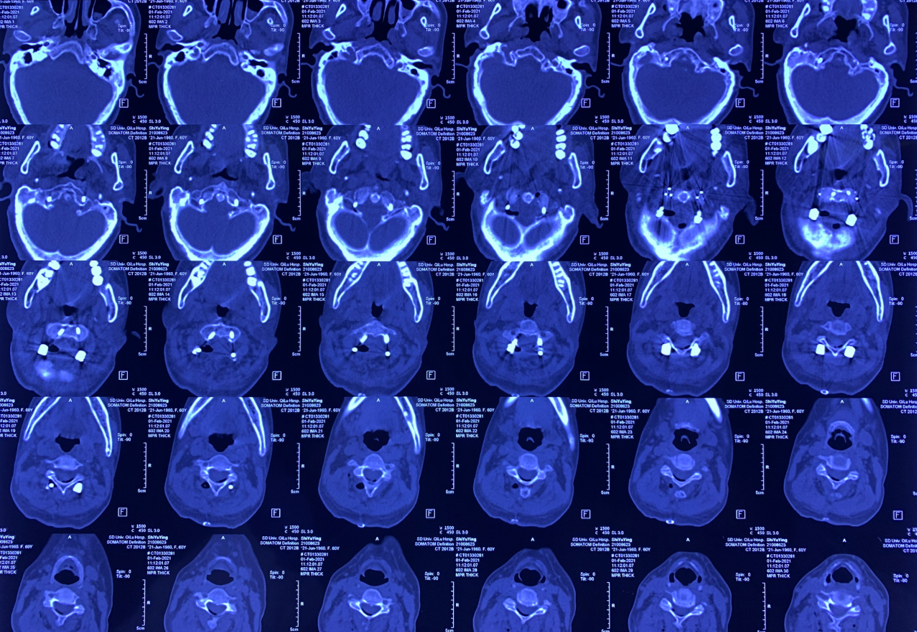

颈椎CT:

颈椎退行性变,C2/3、C3/4、C4/5、C5/6、C6/7椎间盘突出并C4/5水平椎管狭窄;符合颅底凹陷症合并寰枕融合,寰枢关节脱位CT表现。

患者术前部分影像学资料

影像学资料显示寰枢椎脱位,脊髓受压明显